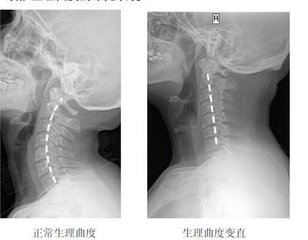

颈椎生理曲度变直:颈椎生理曲度的存在,能增加颈椎的弹性,减轻和缓冲重力的震荡,防止对脊髓和大脑的损伤。颈椎生理曲度变直多由姿势不当而造成,颈椎曲度变直又称颈椎生理曲度消失或颈椎生理曲度反弓。所以这就要求大家平时特别注意自己的姿势,避免造成颈椎病。 》》》百看不如一问,云骨专家在线免费咨询